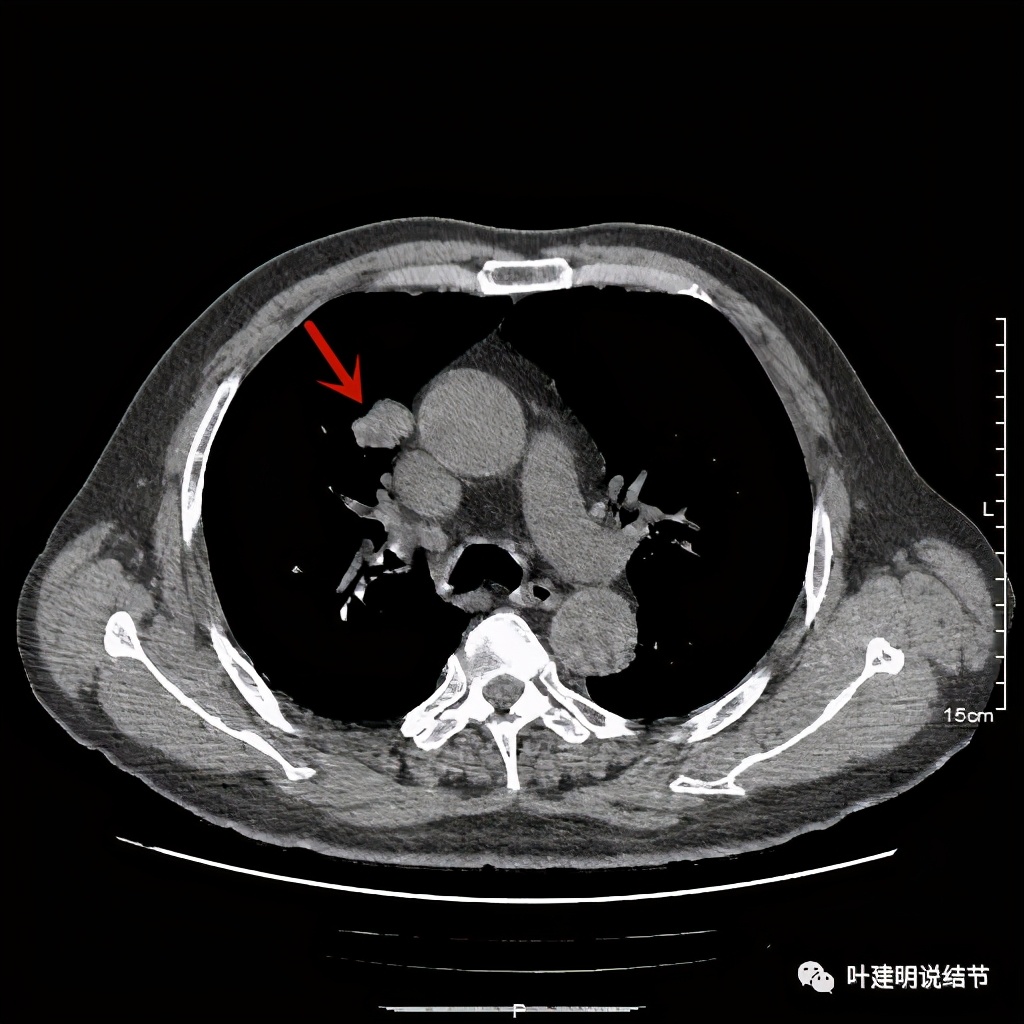

可见右上叶占位,我们现在知道了结果以后回头看,发现病灶的边缘在各个层面都是过于光滑(绿色箭头所示)。血管紧贴病灶边走行(桔色箭头所指),是不是有侵犯看不清楚,若是靶扫描加重建可能会更清楚点。支气管感觉也是贴着病灶走,但有的层面是不是截断,也不看的不太清楚。有的层面见局部有点状高密度(蓝色箭头所指),是不是错构瘤的局部钙化呢?若是纵隔窗又是如何?

上图示病灶边缘过于光滑(绿色);血管贴边(桔色);

上图示病灶边缘过于光滑(绿色);血管贴边走行(桔色)

以上几图也示病灶边缘过光(绿色);血管贴边,感觉没受侵犯(桔色)

4、轻度强化是否可靠?肿瘤达2.4厘米,是否强化会比较明显,因为血供要求较多呀。